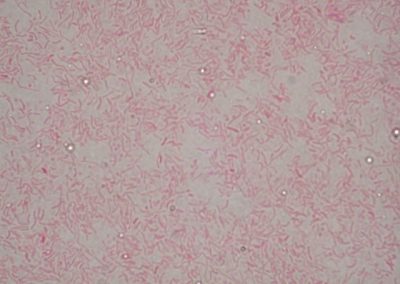

Campylobacter spp.

Rod Campylobacter: Campylobacter spp., kult.

Vibrio spp.

Rod Vibrio: Vibrio spp., kult.